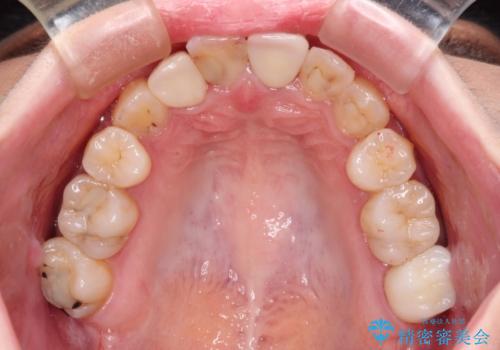

- 奥歯が痛いとのことで来院された患者様です。

上顎親知らず周辺の炎症と、神経組織の失活した歯の炎症による痛みが認められたため、親知らずの抜歯と根管治療を行いました。

根管治療を行った歯はクラウンによる補綴治療が必要となりますが、高校生の頃に行った矯正治療の後戻りも気になるとのことで、補綴治療を行う前に矯正治療を行うこととしました。

後戻りは軽度であり、インビザラインにて歯列を整え、その後にオールセラミッククラウンにて補綴治療を行うこととしました。